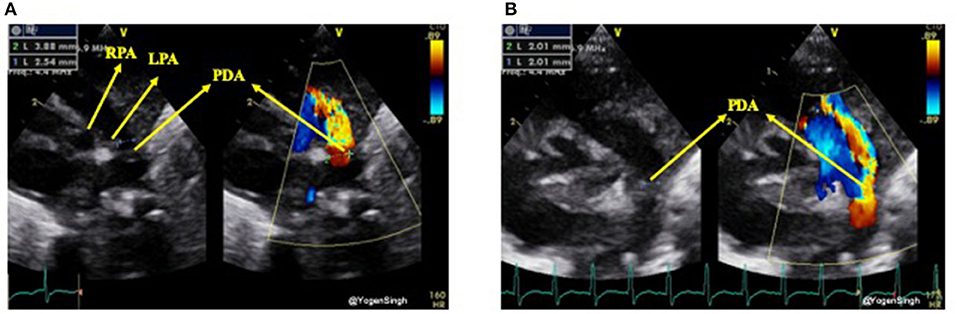

Although the PDA can be visualized from many windows, the high left-sided parasternal “ductal” view is the preferred window to obtain a clear 2D image and accurately measure size of the ductus arteriosus. PDA size is measured from the transductal diameter at the site of maximum constriction (narrowest dimension), which is usually at the pulmonary end (20). Most studies have described measuring PDA size using color Doppler, although with new ultrasound machines and through proper training it can be easily measured on 2D image. If color Doppler is used to measure the duct size the gain setting should be adequately optimized to minimize the risk of over-estimation. Color compare or simultaneous mode, which allows putting 2D and color Doppler image side by side, can be applied to measure ductal size in both modes using frame by frame technique (Figure 3).

Figure 3. Measurement of ductal size on 2D and color Doppler on high left parasternal “ductal view.” (A) Showing significant discrepency between ductal diameter measurement on 2D and color Doppler—over-estimation of ductal size on color Doppler because of gain setting; (B) showing no significant discrepency between ductal diameter measurement on 2D and color Dopple after optimisation of gain setting. LPA, left pulmonary artery; RPA, right pulmonary artery; PDA, patent ductus arteriosus.